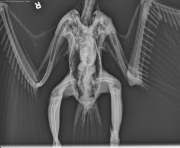

Today’s case is in the special species realm but represents a condition that spans across all species. It’s a 10-week-old Eurasian Eagle Owl with an injury of the left wing noted today. Take a look at the radiographs and post your interpretations.

VD

Multiple projections of the body and wings are available for review. There is overall decreased density of the bone throughout the body. There are folding fractures present of the proximal left ulna and radius, of the proximal left humerus, and of the proximal right tibiotarsus. There is also a markedly heterogeneous appearance of the distal aspect of the left ulna consistent with a chronic fracture. There is soft-tissue swelling surrounding the left radius / ulna and right tibial fracture sites.

Diffuse osteopenia with multiple folding fractures suspected to be pathologic of the left radius, ulna, and humerus and of the right tibiotarsus. Given the signalment, nutritional secondary hyperparathyroidism should be a top consideration. Other causes of diffuse osteopenia such as hereditary conditions or metabolic imbalances should be considered.

Dietary calcium:phosphorous imbalance can cause poor skeletal mineralization and pathologic folding fractures. The mechanism is most often secondary hyperparathyroidism.

Transition to a whole prey diet with calcium supplementation was recommended. The wing was bandaged as the poor bone quality was not suitable for internal fixation.